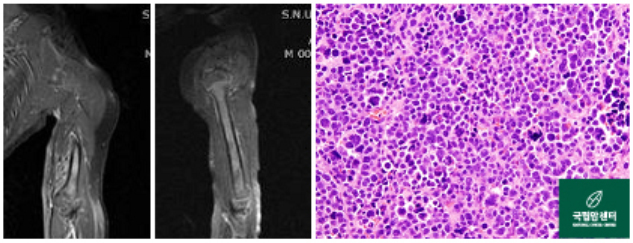

[ 왼쪽 상완부에 횡문근육종을 가진 환아의 사진 ]

[ 위 환아의 항암약물치료 후 사진과 병리 사진 ]

원발 병소의 자기공명영상(MRI)을 포함하여 전이의 배제를 위하여 전신검사가 필요합니다.

전이율이 높고 전이는 폐, 림프절, 골수에 흔하며, 원발병소가 사지인 경우 림프절 전이가 20% 정도로 흔합니다. 횡문근 육종은 주위 구조물에 침습을 잘하는 공격적인 종양으로 뼈에도 침습을 잘하기 때문에 외과적 절제연을 결정하기가 어렵습니다. 수술적 치료로는 광범위 절제술을 하여야 하며, 근치적 치료 후에도 재발이 되거나 조기에 폐나 림프계로 잘 전이하므로, 방사선 치료와 항암제 투여를 병행하여야 합니다.